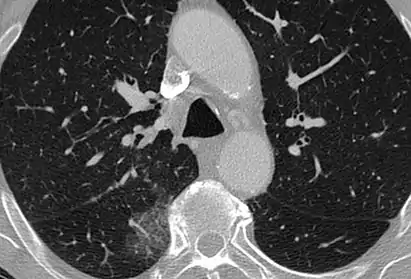

CT image showing ground-glass opacification in the posterior of the right lung (screen left). - Measles

CT image showing diffuse GGOs throughout both lungs. An abscess is also noted in the right lung (screen left). - Adenocarcinoma in situ of the lung